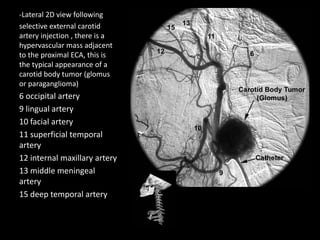

1-ICA , 2-MCA , 3-ACA (A1) , 4-ACA (A2) , Arrow : ACOM

1-Straight sinus , 2-Internal cerebral vein , 3-ACA (A2) , 4-ACA (A3) , 5-

Callosomarginal artery , 6-Pericallosal artery , 7-Corpus callosum